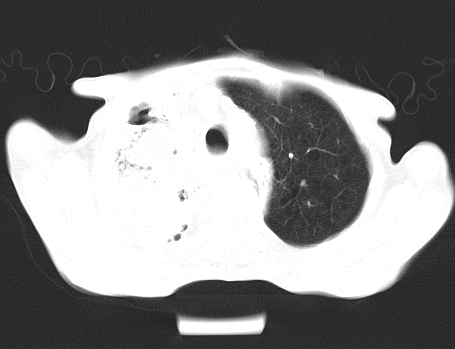

以下是引用深泽交通医院在2008-5-25 9:53:00的发言:[br]右肺炎症;纵隔淋巴结肿大,考虑转移;左侧术后胸腔胃

以下是引用gaoshengjiang在2008-5-30 19:53:00的发言:[br]右上叶可见大片实变影,其内可见充气支气管影及囊状影,右上叶尖端支气管走形区可见结节样影,左侧胸腔内可见胸腔胃影。纵隔淋巴结肿大。[br]考虑:1.右上肺阻塞性肺炎伴肺脓肿形成。支持转移所致。[br] 2.左侧胸腔胃。